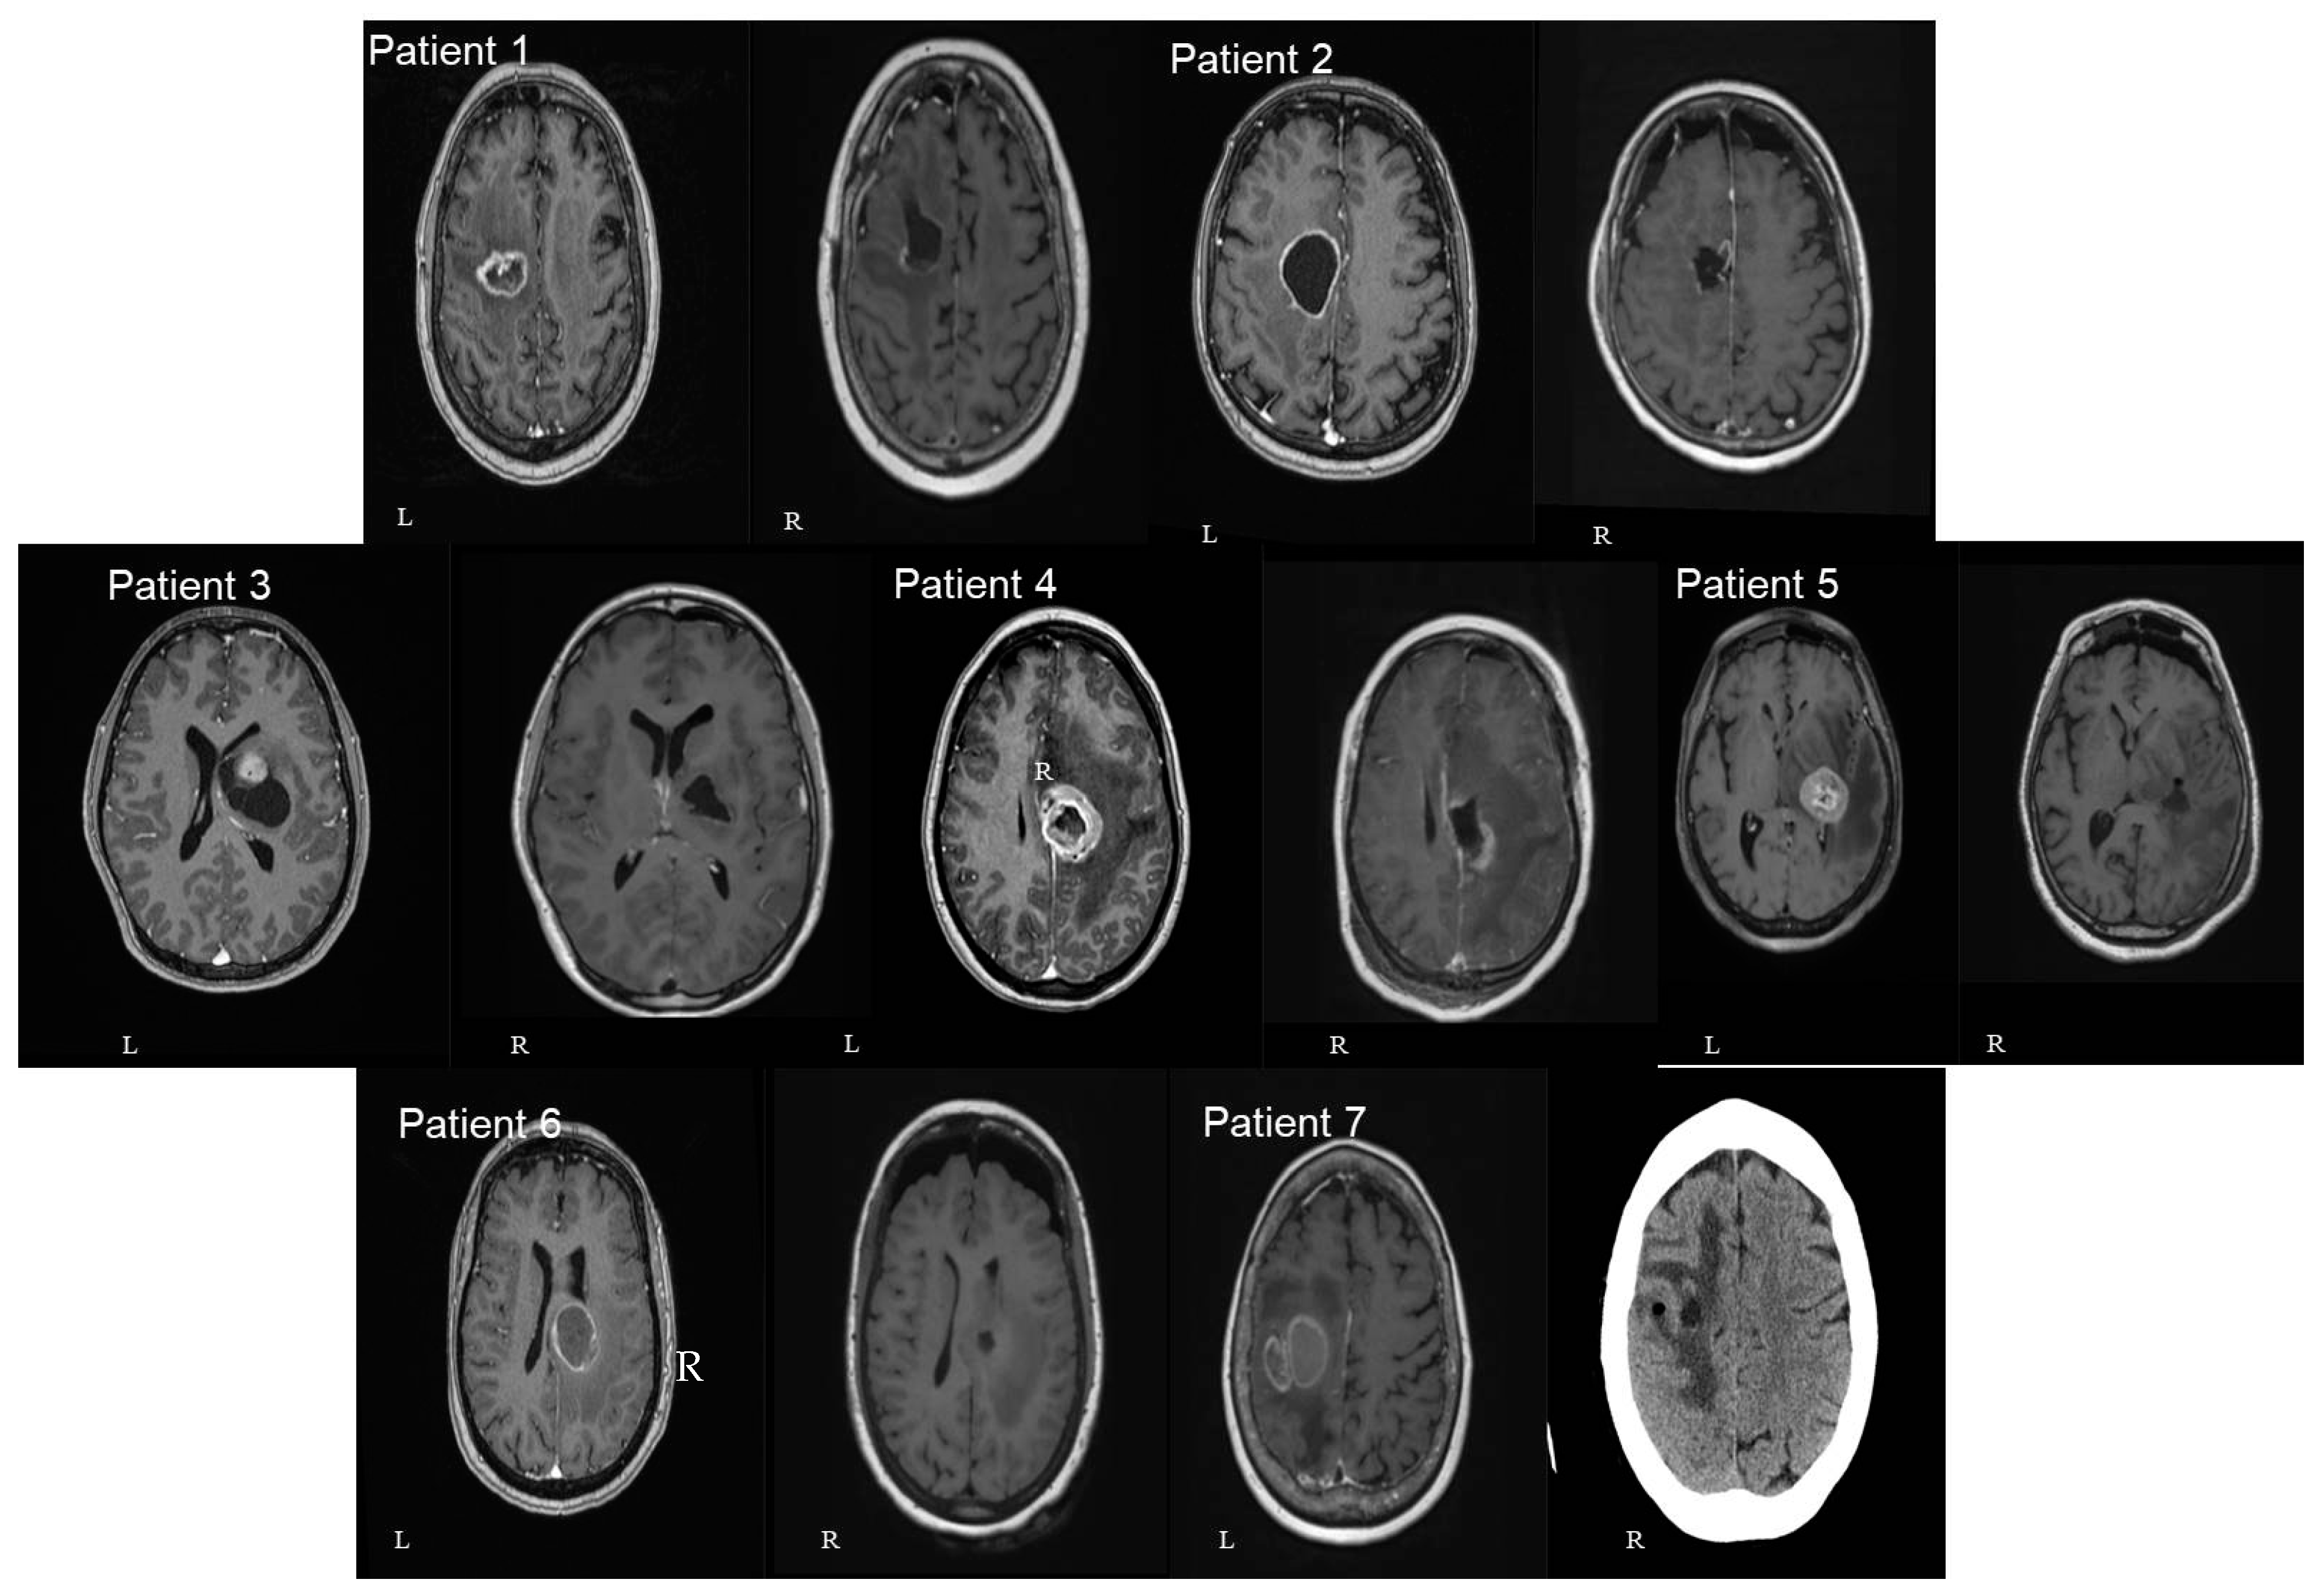

In three patients the lesion was located at the cingulate gyrus. In two of them, the tumor was centered in the precentral gyrus, and in the final two, at the basal ganglia involving the thalamus and the internal capsule. Four patients had left-sided lesions and three had right-sided lesions. The mean distance between the lesions and the cortex as measured in the preoperative MRIs was 30.9 mm (range: 7 mm–46 mm) (Figure 3 and Figure 4). The mean volume of the included lesions was 13.2 cm3 (range: 3.3–32.6 cm3).

Figure 4. Axial (left—L) and sagittal (right—R) T1 gad MRI brain images of all seven patients included in our study. In 3 patients the lesion was located at the cingulate gyrus (numbers 2, 4, and 6). In 2 of them, the tumor was centered in the precentral gyrus (numbers 1 and 7). In the final 2 patients, the lesion was centered at the basal ganglia involving the thalamus and the internal capsule (numbers 3 and 5). The number of patients in each image corresponds to the patients mentioned in Table 1.